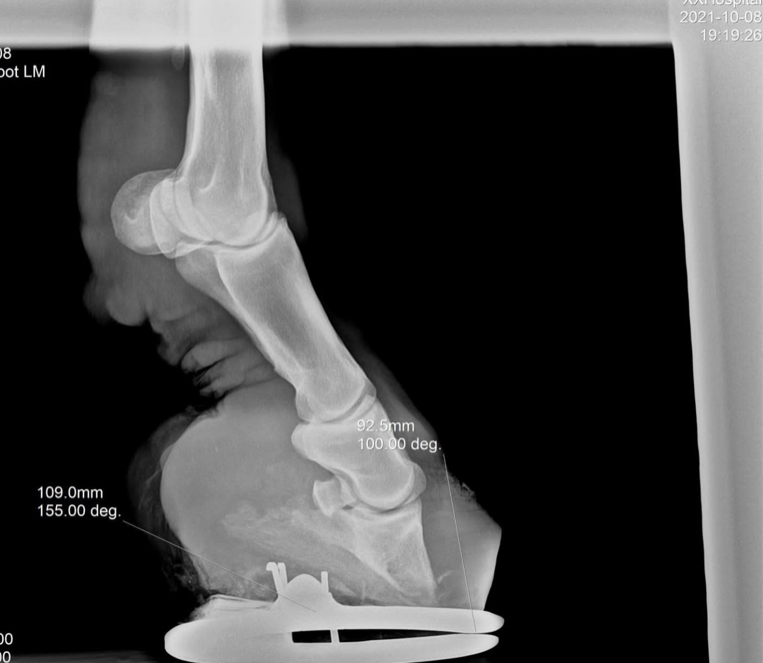

18 лет, забрала из максимально херовых рук. Не ходил, ел овёс и пасся

Сейчас мы пытаемся ходить, наблюдаемся у разных врачей, набираем вес(истощенный пипец), даю ему ламинатор(почти закончился, посоветуйте другие подкормки), масло льна, биотех-ц «сбор при ламините», и лактобифадол(если сильно больно ему, колим неуротранк+флуниджект)

+ортопедическая ковка